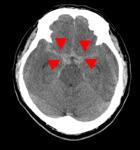

頭部CT検査

十数秒の撮影で、脳内の状態を知ることできます。

画像例では、脳の正常部分に対して白く描出されている部分があることで、脳内出血、くも膜下出血が起きていることがわかります。

反対に、黒く描出されている部分があることで、脳梗塞が起きていることがわかります。

画像の濃淡を調整すると、頭蓋骨骨折の有無を確認することもできます。

また、造影剤を注射しながら撮影することで、動脈瘤や腫瘍などのより詳細な観察が可能になります。